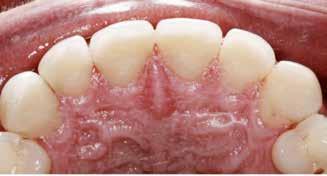

Klinisk undersøgelse viste emaljehypoplasier og hypomineralisering på 1+, +1, 2-, 1-, -1 og -2 (Fig.1). Hun havde Angle klasse II, pladsmangel i begge kæber og agenesi af -5. Der var isninger ved spisning og tandbørstning. Fundene var forenelige